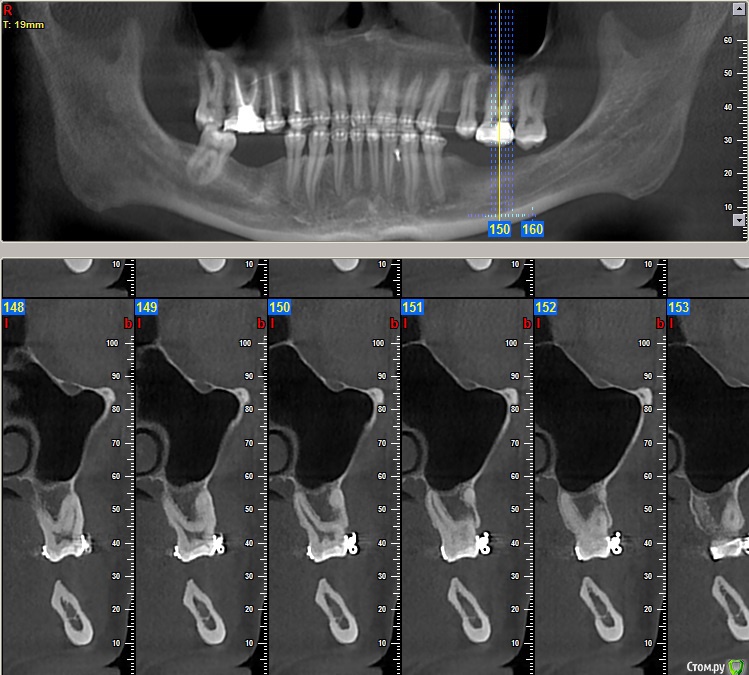

Dionis Опубликовано 13 августа, 2015 Поделиться Опубликовано 13 августа, 2015 Добрый день. Прошел 4х годичный курс лечения ортодонтии. Все готово. Но перед съемом брекетов остро стоит вопрос имплантации. Ортодонт говорит, что нельзя снимать без готовых имплантатов, т.к. могут разъехаться обратно. Прикладываю 4 снимка: до лечения, и 3 снимка КТ с освободившимися местами под имплантаты после лечения. Прошу совета у знающих специалистов:1) В какой последовательности все делать? Очень хочется максимально быстро снять брекеты - сил больше нет(((2) Сколько имплантатов ставить и куда?3) Хватит ли кости справа внизу?4) Посоветуйте, пжста, как выбрать специалиста (-ов), можно в личку. Посетил 3 консультации, две из трех никуда не годятся (доктора не понравились - навязчиво втираются в доверие и ведут себя странно, да и стоимость запредельно выше рыночной). Один доктор понравился, но много негативных отзывов в нете о клинике, как и позитивных, да и видно обилие липовых и левых отзывов, хвалящих самих себя (одни и те же отзывы на разных форумах под разными именами, отзывы с одного айпи и т.д.). Плюс не знаком ещё с ортопедом, который работает в паре... Пока рассматриваю. Буду очень признателен за любую ценную информацию! С уважением,Денис из Москвы Ссылка на комментарий

Dionis Опубликовано 14 августа, 2015 Автор Поделиться Опубликовано 14 августа, 2015 Очень хотелось бы услышать мнения профессионалов по первым трем вопросам:1) В какой последовательности все делать? Очень хочется максимально быстро снять брекеты2) Сколько имплантатов ставить и куда? Ваше мнение очень интересно по поводу нижней челюсти!3) Хватит ли кости справа внизу? Если не хватает, то какой вариант возможен для увеличения (пластика какая именно)? Насколько сложный случай? Судя по КТ, по правому низу в районе 5ки ещё и нерв выходит из челюсти - вчера был на приеме у хирурга, где меня предупредили, что при пластике будет потеря чувствительности из-за разрыва... Насколько это серьезно? Чем чревато в будущем? Совместно с хирургов выработали вариант имплантации 6го с консолью на 5ый. Какие ещё мнения возможны? Спасибо за Ваши ответы,С уважением,Денис Ссылка на комментарий

faity Опубликовано 19 августа, 2015 Поделиться Опубликовано 19 августа, 2015 посмотрел КТ, качество и удобство конечно редкостное...)))проблем не увидел особых, справа импланты, слева импланты и операция по костной пластике. через полгода будете уже ими жевать.только нужно будет КТ переделать, потому что для качественного планирования этого недостаточно.а правильное планирование это половина лечения.по этапам: гигиена(при необходимости), имплантация, через 4 месяца снимать слепки, когда будут готовы коронки- снимать брекеты и фиксировать коронки. но в любом случае надо смотреть Ссылка на комментарий

Dionis Опубликовано 19 августа, 2015 Автор Поделиться Опубликовано 19 августа, 2015 Спасибо большое. Пластику хочу на попозже немного отложить. Слева внизу в области 5ки неоднозначная ситуация с выходом нерва. Боюсь как бы не повредить. Чувствительность не хочу терять. Можете еще подсказать, пожалуйста:1) хватит ли расстояния для имплантата сверху между зубами? Каковы риски повредить здоровые зубы?2) достаточно ли расстояния снизу справа до нерва? Можно ли обойтись без пластики там?3) что не так с этим КТ? Почему нужно будет переделать? Ссылка на комментарий

faity Опубликовано 20 августа, 2015 Поделиться Опубликовано 20 августа, 2015 начну с последнего вопроса3)КТ не информативно, субъективно на мой взгляд, из-за нечеткой картинки и убогости интерфейса ПО.2)скорее всего можно1)не смог разглядеть Ссылка на комментарий